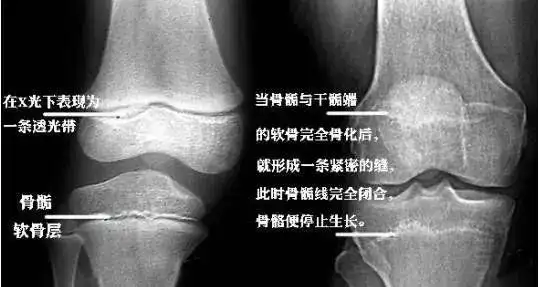

五,骨的生长发育 骨的变长:骺软骨的骨化. 骨的变粗:骨膜的骨化.

一种我们叫软骨生长,长骨的末端有一个软骨板,也叫骨骺板